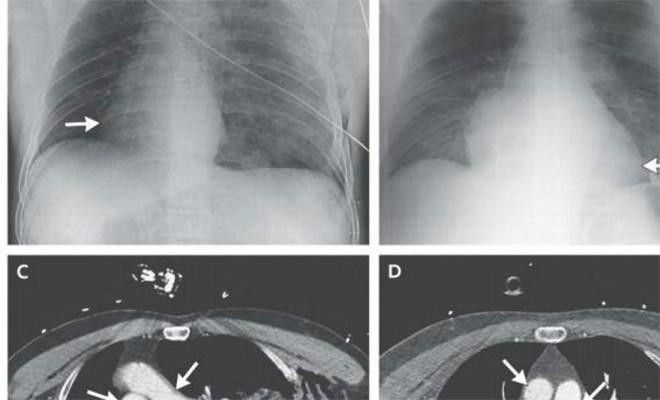

Повернувшееся сердце

9

В 2014 году, попавший в аварию итальянский мотоциклист поступил в больницу с необычными симптомами. Его сердце стало биться с перебоями и медленнее, чем обычно. Обследовав мужчину, врачи с удивлением обнаружили — сердце парня повернулось на 90 градусов в правую сторону. Это состояние называется декстрокардией, врожденным дефектом, прецедент с аварией был первым. К счастью, докторам удалось обратить изменения.